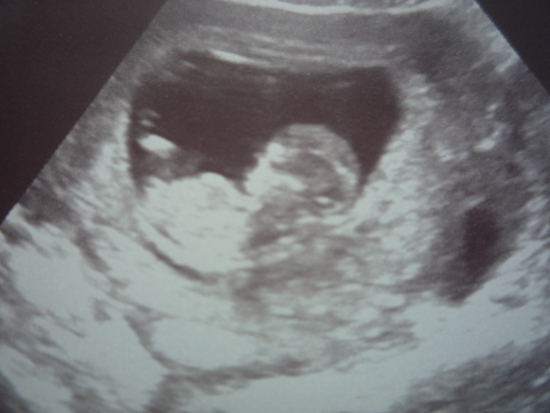

Сегодня ходили на УЗИ мы уже 4см8мм, крутился как веретено, ножками отталкивался так меня это умиляло, а еще я услышала как бьется сердечко мое родное 160 ударов в минуту. Хотели пол посмотреть, но у нас была пуповинка между ног, так что не захотел он нам раскрывать тайну =)

А так результат конечно не точный будет, лучше в 18 недель узнавать пол =)